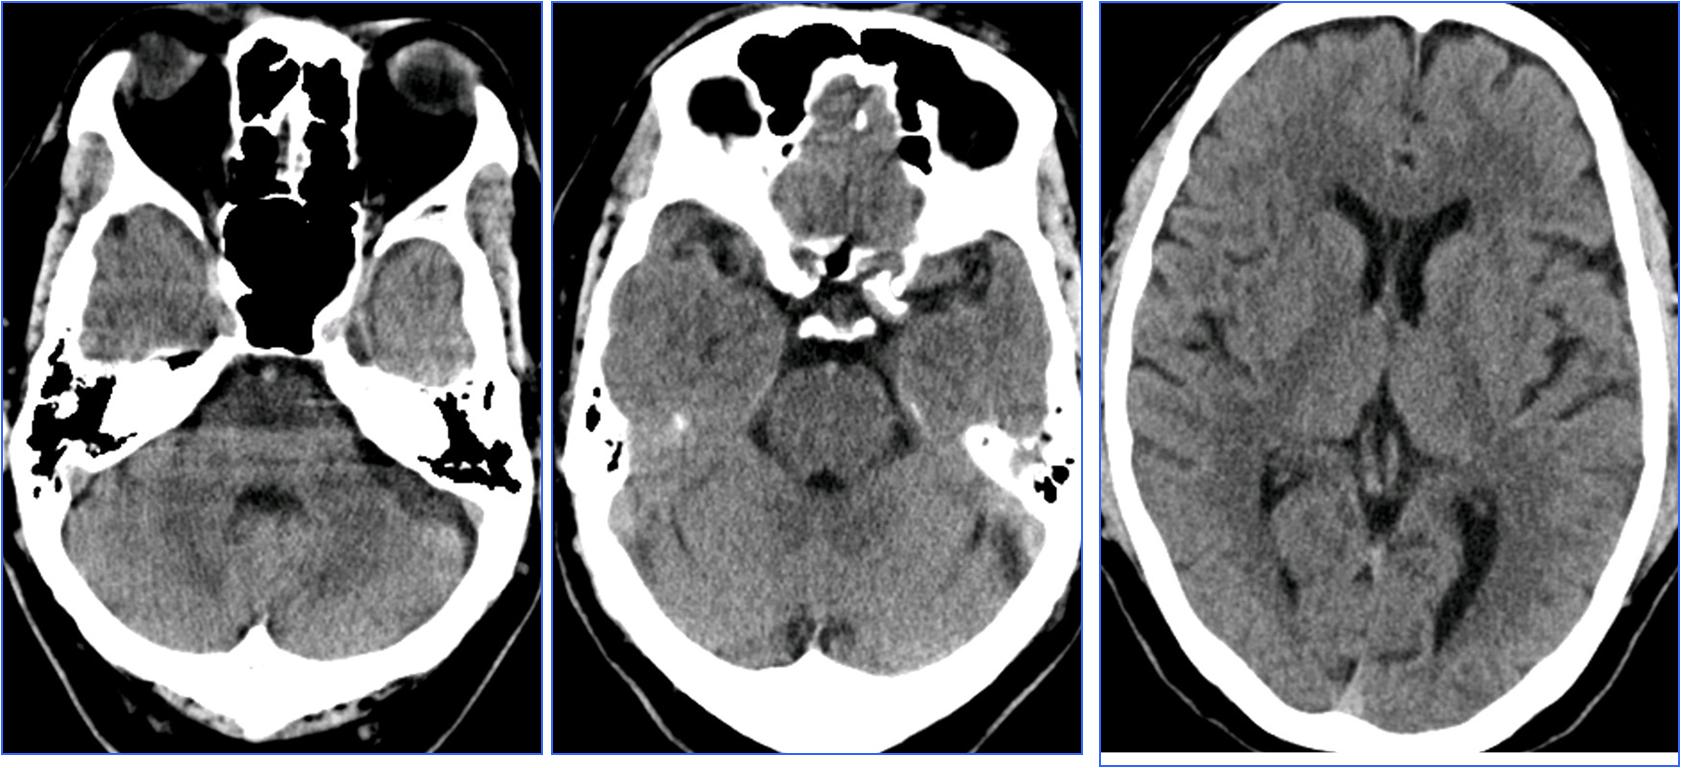

▼术前CT

▼术前MRA

▼术后24h头CT

▼术后72h 病情恶化,脑疝形成

▼去骨瓣减压,死亡